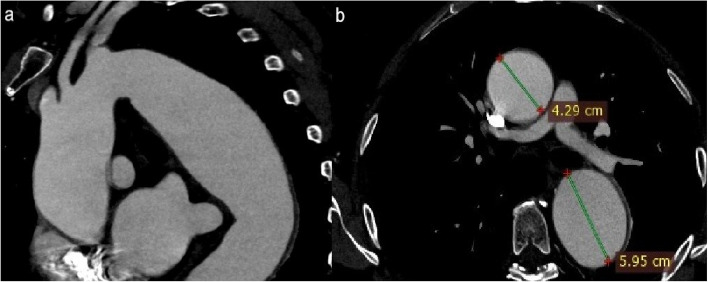

Background: Thoracic endovascular aortic repair (TEVAR) has been a feasible treatment option since the first stent graft was approved by the FDA in 2005, and is now the recommended method for treating most descending aorta pathology in the current clinical practice guidelines. Indications for TEVAR include descending aorta aneurysms, traumatic aortic injury and pathology that presents as acute aortic syndrome. More often than not the lesion that needs to be excluded is quite close or contains the distal aortic arch, thus requiring the coverage of the left subclavian artery (LSA) origin, a practice that has been associated with severe complications. Contraindications to LSA coverage resulted in the development of various surgical and endovascular LSA revascularization techniques.

Materials and methods: Branched stent grafts containing a single branch for the LSA are a rapidly evolving technology regarding LSA reconstruction during TEVAR. The aim of this article is to demonstrate our center's experience using a novel off-the-shelf single-branched stent graft, the GORE® TAG® Thoracic Branch Endoprosthesis (TBE) (W. L. Gore & Associates, Inc, Flagstaff, Ariz, USA). The GORE® TAG® TBE is commercially available in Europe since early 2024. We have so far, since February 2024, treated 12 patients using this endograft, successfully treating all types of aortic lesions.